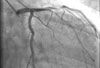

A 72-year-old obese man with chronic atrial fibrillation, hypertension, hyperlipidemia, and a history of tobacco use presented for a routine office visit. A year earlier, he began to experience recurrent chest pain, but an ECG had shown normal T waves.

According to the Sgarbossa criteria, the patient had an acute MI: ECG revealed a greater than 1-mm ST-segment depression in lead V2 and about 5-mm discordant ST-segment elevation in leads II, III, and aVF.